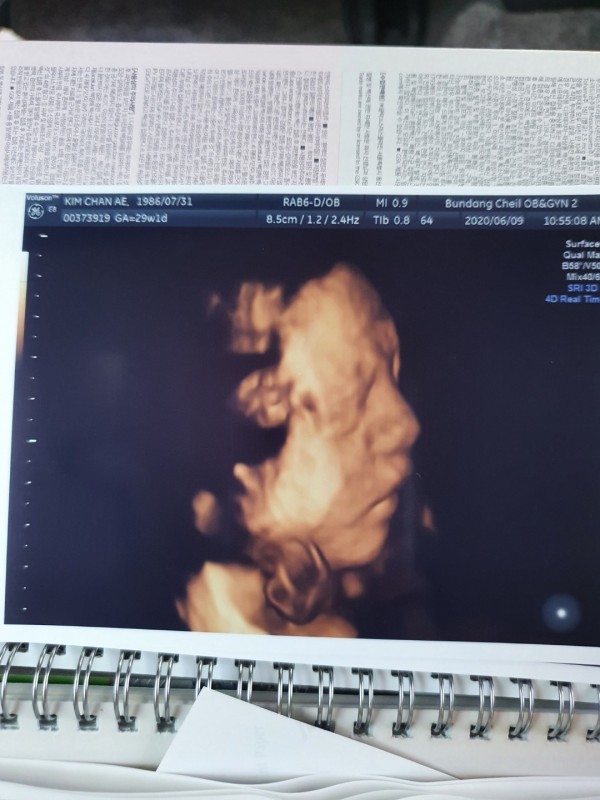

또한 주수에 맞춰 진찰에 가면 꼼꼼하게 초음파도 봐주시고 다양한 조언으로 무사히 37주에 접어들 수 있었습니다. 5월초에 입원 시에 다른 출산 후 입원한 산모들을 보며 부러워도 하고 언제 저희도 저 시기가 오나 많은 걱정도 하고 막막했지만 위혜정 선생님의 도움으로 인해 위험한 시기도 넘기고 오히려 지금은 아기가 너무 크지 않을까 걱정할 정도로 안정적인 상태가 되었습니다.

2020-08-13안녕하세요. 재현님! 이렇게 사랑이의 모습이 담긴 초음파와 예쁜 메모가 적힌 사진을 감사의 편지와 함께 보내주시어 너무 감사합니다. 사랑이에게 보내는 편지 속에서 사랑과 행복이 가득 전해지는 듯 합니다. 10달 가까이 되는 시간 동안 당황하고, 걱정되셨을 순간 또한 무사히 보내시어 이렇게 따뜻한 감동이 담겨 있는 감사의 말씀을 듣게 되어 도리어 본원 의료진 및 직원들이 더 큰 행복을 느낍니다. 사랑이와 만나는 순간까지 더욱 더 안전하고, 건강하실 수 있도록 노력하겠습니다. 감사합니다.